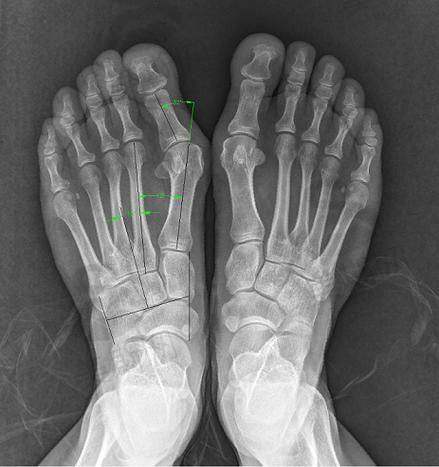

首先是术前评估,医生会对患者进行详细的检查,包括足部X光检查、步态分析等。通过这些检查,医生可以全方面了解患者的病情,从而确定更适合的手术方案。这就像是在盖房子之前,先对地基进行详细的勘察,确保房子能够稳固地建造起来。